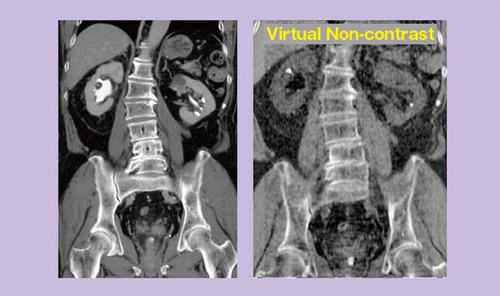

また逆に,各ボクセルでのヨード造影剤の影響を取り除けば,脂肪と軟部組織の混合比に基づいた実質臓器のCT値が推定できる(図4)。これに基づいて作成されるのがVirtual Non-contrast画像である(図5)。例えば,尿路に造影剤が排泄されてしまった造影後のデータからも,尿路の造影剤を取り除いて結石を描出することが可能になると期待される。

図4 Virtual Non-contrastの原理

図5 Virtual Non-contrast画像

CTUの造影前撮影をVirtual Non-contrastで代用できるのではという期待がある。われわれの検討では,単純CTで検出された32個の尿路結石のうち,造影後のCTUで検出できたのは5個だったのに対し,Virtual Non-contrastでは16個と,より多くの結石が検出された。しかし,2〜3mmの小さい結石や吸収値が低い結石など,現時点でVirtual Non-contrastでは,すべての結石を検出することは困難であると思われる。

図6 無症候性肉眼的血尿症例のVirtual Non-contrast画像(右)